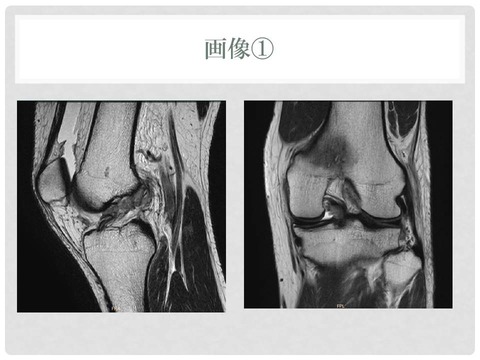

医療機関によるレントゲンなどの画像診断は済んでいます

スライド6